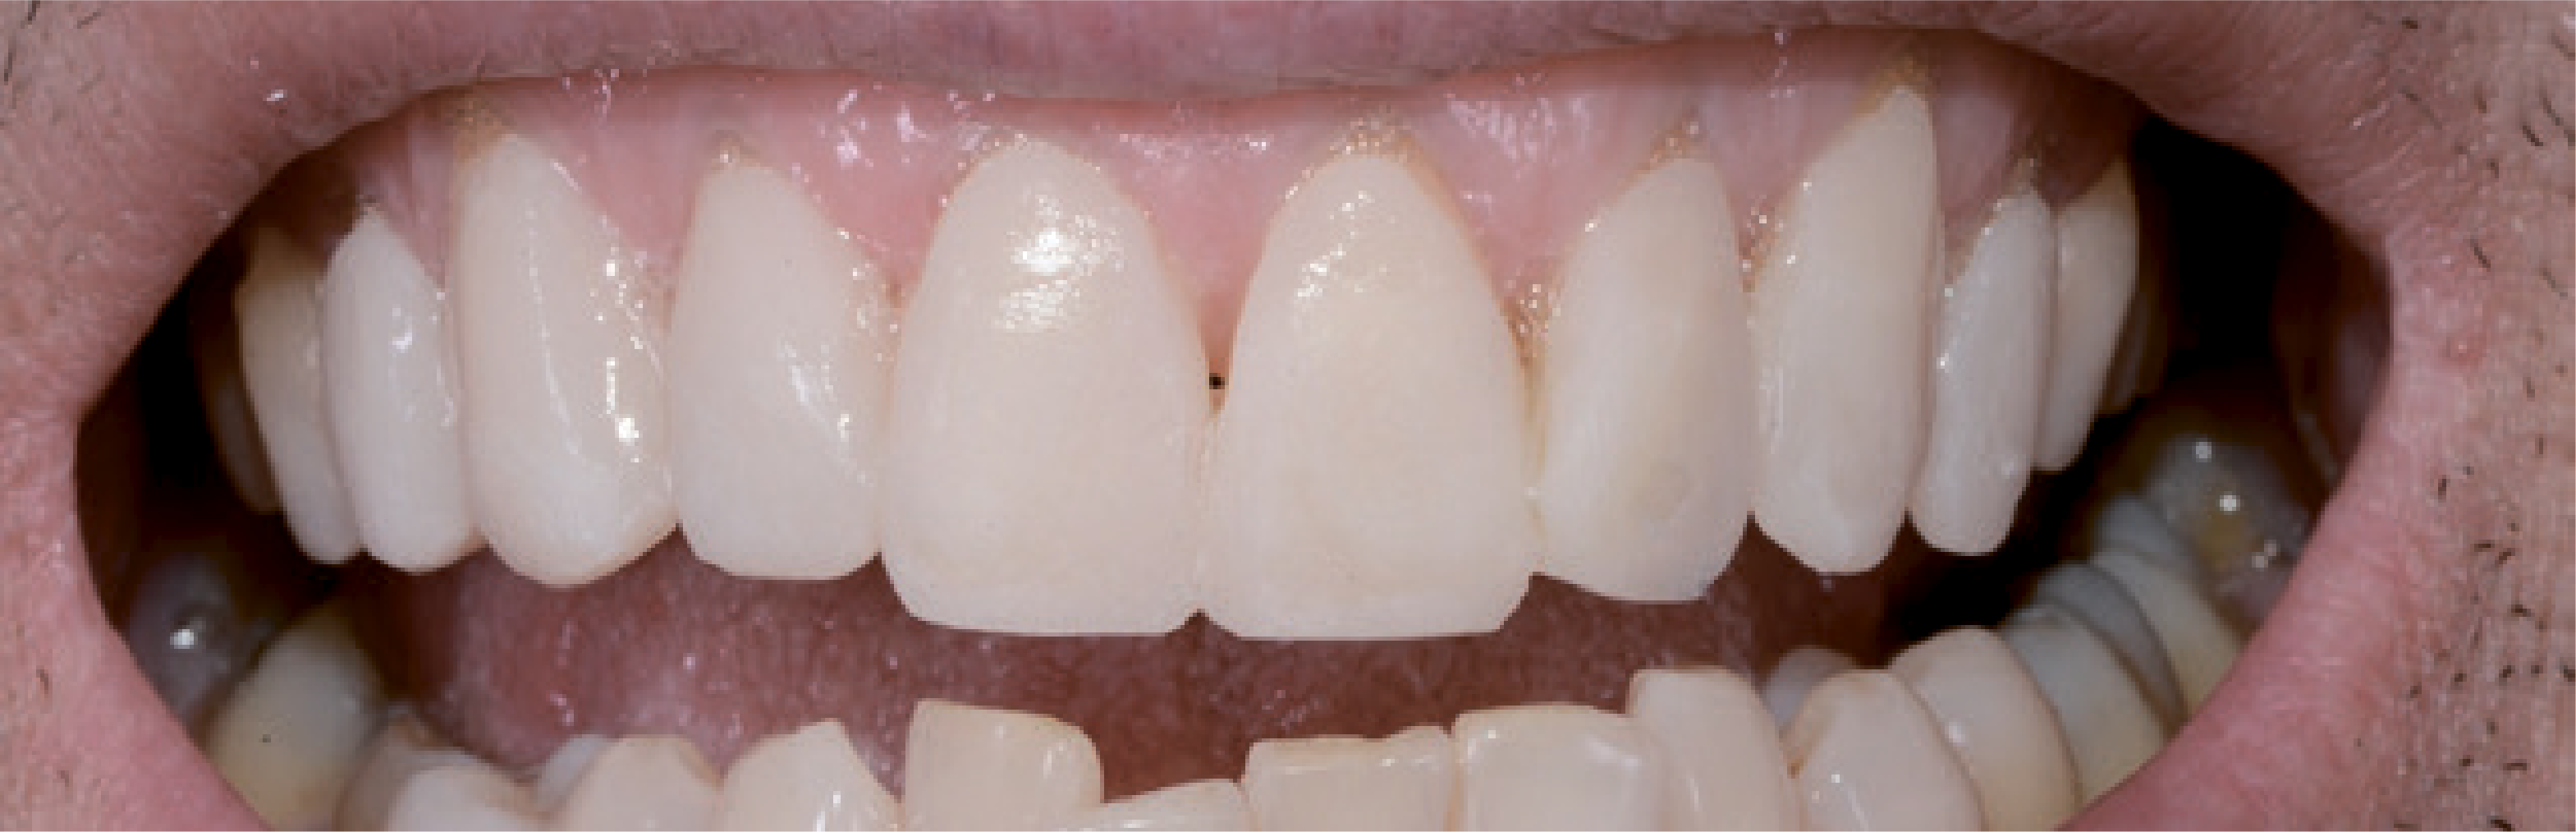

Перш за все, була змодельована вестибулярна поверхня, щоб дізнатися, яким буде естетичний вигляд посмішки. Після фотополімеризації змоделювали функціонуючу різцево-піднебінну зону з нанесенням контурів статичної та мобільної оклюзії. У цьому випадку, на цьому етапі не було потреби відтворювати сагітальний різцевий шлях, тому що на другому етапі робіт дугу нижньої щелепи необхідно вирівняти за допомогою ортодонтичних процедур, а потім – закрити вінірами. Формували модель у напрямку від верхнього правого першого премоляра до верхнього лівого першого премоляра, щоб рівномірно заповнити «щоковий коридор» (мал. 4).

Навіть досить кваліфіковані стоматологи зовсім не завжди вирішуються використовувати вініри для естетичної реставрації. Вони бояться не отримати бажаний естетичний результат, адже пацієнти дуже вимогливо ставляться до такої процедури, оскільки вони змушені чимало за неї заплатити. Психологічна сторона, пов'язана з естетичною зоною, є непередбачуваним фактором ризику. Завдяки двоетапній техніці прямого й непрямого mock-up естетичний результат можна обговорити з пацієнтом, а потім і реалізувати його за участю пацієнта. Коли модель mock-up виглядає достатньо переконливо для стоматолога й пацієнта, вона використовується як якісний орієнтир для отримання задовільного естетичного результату. Далі препарування виконується виключно в межах емалі – для надійної фіксації реставраційної конструкції адгезивним цементом на тривалий термін. З цієї причини згодом, щоб створити оптимальне з’єднання, поглиблення не препарували. У цьому випадку ці ділянки непомітні крізь лінію посмішки, і пацієнт не захотів, щоб контури виправляли мікрохірургічним шляхом. В інших випадках оптимізувати естетичний вигляд м'яких тканин можна за допомогою вільного слизового трансплантата. Новий сагітальний різцевий шлях був створений за допомогою вінірів, щоб не допустити впливу неконтрольованих зусиль. Вночі ж щелепно-ротовий апарат і реставраційні конструкції були захищені за допомогою верхньощелепної ортопедичної капи. Активне спілкування і взаємодія стоматолога з пацієнтом спочатку передбачає виконання додаткової роботи, проте допомагає швидко отримати прогнозований результат і виключити непередбачені витрати коштів і часу, а також непотрібний стрес і розчарування (мал. 21 і 22).